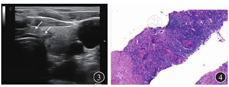

患者女,38岁,因"体格检查发现双肺多发占位3 d"于2019年10月21日入院。患者无咳嗽、咳痰、发热、盗汗等症状,体格检查示:甲状腺无肿大、压痛;全身浅表淋巴结未触及;呼吸运动正常,双肺呼吸音清,无干湿性啰音。入院后完善相关检查。超声检查示:甲状腺双侧叶实性结节[甲状腺影像报告和数据系统(throid imaging reporting and data system,TIRADS)分级为4a级,建议行超声引导下细针吸取(fine-needle aspiration)],甲状腺右侧叶囊实性结节(TIRADS分级为3级),见图1。胸部CT检查示:甲状腺双叶低密度结节,双肺多发结节,见图2。PET-CT检查示:双肺多发结节代谢较活跃,甲状腺双叶多发低密度结节代谢活跃。T-SPOT.TB示抗原A[早期分泌抗原靶-6(early secretory antigenic target-6,ESAT-6)]孔斑点数为56个,抗原B[培养滤液蛋白10(culture filtrate protein 10,CFP-10)]孔斑点数为50个;抗酸染色未见抗酸杆菌;血清三碘甲腺原氨酸(triiodothyronine,T3)、甲状腺素(thyroxine,T4)、游离三碘甲腺原氨酸(free triiodothyronine,FT3)、游离甲状腺素(free thyroxine, FT4)、促甲状腺激素(thyroid-stimulating hormone,TSH)均正常,结核特异性分泌抗原抗体、结核分枝杆菌抗体IgM及IgG均为阴性。行超声引导下甲状腺结节穿刺细针吸取细胞学检查(图3),在多普勒超声引导下以22 G穿刺针进入结节,反复提拉,快速对结节抽吸约10~15次,并旋转针尖,取病灶的不同部位,抽出物以液基固定送病理检查。采用无菌棉球覆盖穿刺部位,按压5~10 min以防出血。病理检查显示:甲状腺右叶下极肉芽肿性炎伴坏死,结核不除外,见图4;甲状腺左叶下极考虑结节性甲状腺肿;肺穿刺活组织病理检查示肉芽肿性炎伴坏死,倾向结核,见图5。结合临床病史,以及实验室、影像学检查,基本可以诊断为肺结核合并甲状腺结核。